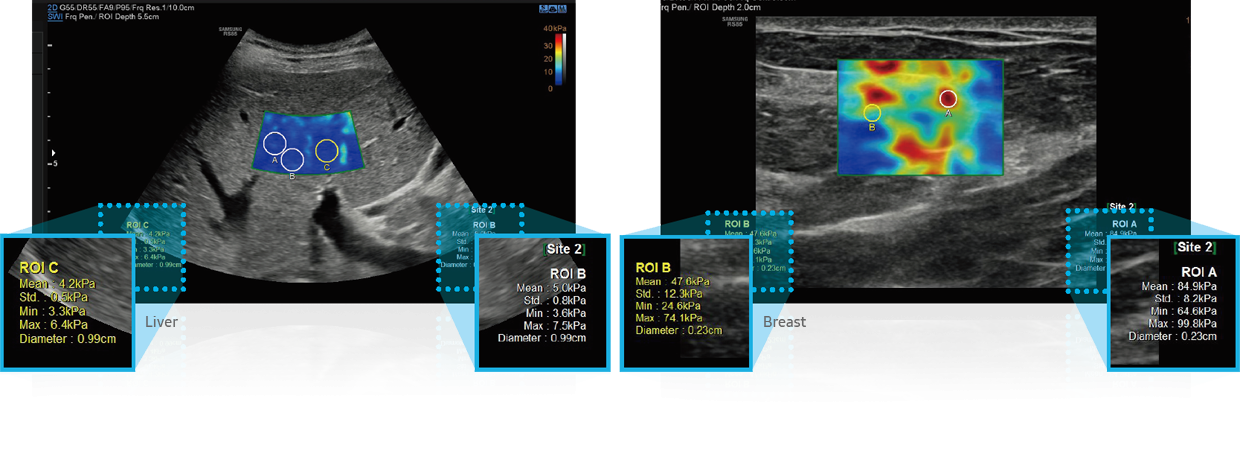

S-Shearwave Imaging ™

Neinvazivní metoda kvantifikace tuhosti tkáně

S-Shearwave Imaging ™ umožňuje neinvazivní hodnocení tuhosti tkáně / lézí v prsu a játrech, poskytnutím pokročilé úrovně diagnostických informací. Barevně mapovaný elastogram, kvantitativní měření (inkPa nebo m / s), možnost duálního zobrazení a uživatelem volitelné funkce ROI (pozice a velikost) jsou obzvláště užitečné pro přesnou diagnostiku onemocnění prsu a jater.